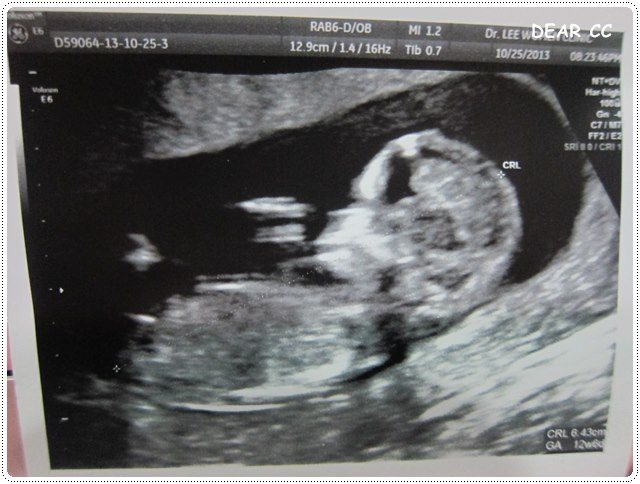

隔一周10/25

早早預約去聽報告

原本以為只是聽醫生講解一番

結果醫生還是幫我們照了超音波

儘管我天天吐得唏哩嘩啦,蕭CC還是有隨著週數長大,真開心

然後,唐氏症的風險是接近六千分之一

機率好像很小